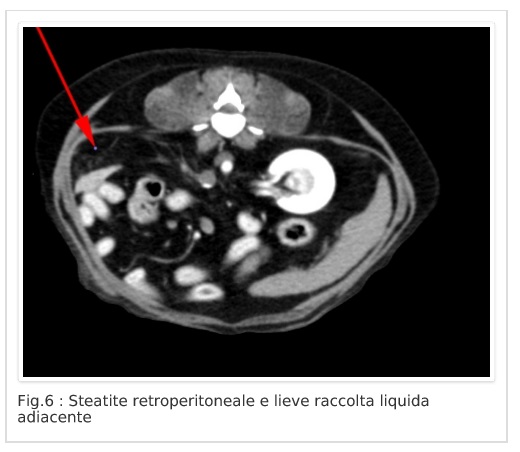

Neoformazione surrenalica destra e steatite retroperitoneale.